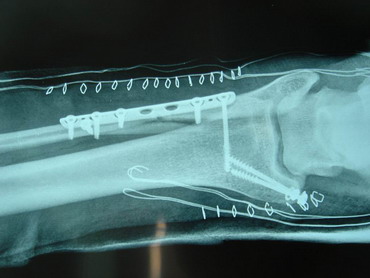

14 - 5 - 07 El torero se interviene hoy a la 12,30 horas en la Clínica Sagrado Corazón de Sevilla. Se confirma diagnóstico provisional hecho en la enfermería de la plaza de Osuna. Fractura de tibia y peroné. Con las siguientes connotaciones: La fractura de peroné es completa y compleja consta de 4 fragmentos diferentes con desplazamiento de los mismos. es decir una fractura conminuta. La tibia presenta fractura maleolar con desplazamiento y además con respecto al tobillo existe una subluxación de la articulación debida a la rotura o explosión de la cápsula articular con desflecamiento de la misma. En resumen un cuadro complejo de tobillo inestable que precisa intervención quirúrgica inmediata. Se estabilizan las fracturas, se sutura la cápsula anterior, se reduce la subuxación, se administran factores de crecimiento y se inmoviliza extremidad. Pronóstico grave. Se estima un tiempo de recuperación de 90 días. Dr. Minguet. Dr. Periañez. Dr. Vaz. Dr. Morales |